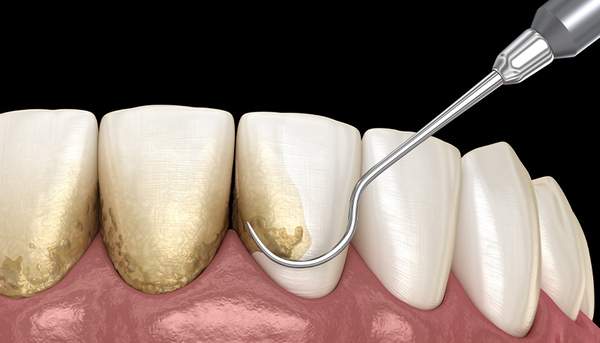

定期検診、歯科医院に何も症状がなくても半年に1度は、行くことをオススメします。多くの歯科医院で虫歯になる前に定期検診を受けましょうということで、予防歯科を掲げる歯科医院が増えました。では、3〜6ヶ月に1度の定期検診で何をするのかというと虫歯や歯周病のチェックはもちろんですが、PMTC(プロフェッショナルメカニカルトゥースクリーニング)を行います。横文字が並ぶと何がなんだか?わからないですよね。簡単に言えば、歯に付着する細菌を落としてあげることです。

これでもわかりにくいですよね。そう!台所の三角コーナーのヌメヌメを取るような感じで歯科医院に来院してもらいます。歯と歯の間にもあのヌメヌメが付着するんですね。それを定期的に除去すると虫歯や歯周病の確率が約1/8になると言われています。日々のご自分での歯ブラシは、もちろん重要ですが、歯科医院での定期検診も非常に虫歯予防に重要となりますので覚えておいてください。